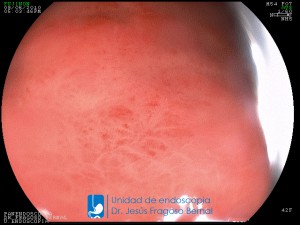

La Unidad de Endoscopía fue creada en 2002 por el Dr. Jesús Fragoso Bernal, es pionera en el estado por la utilización de la tecnología más avanzada, que nos permite ofrecer servicios integrales de diagnóstico y tratamiento para las enfermedades del aparato digestivo.

"La Unidad de Endoscopía se ha caracterizado por un progreso continuo desde su inicio marcando la pauta en los procedimientos endoscópicos en el estado de Tlaxcala y estando siempre a la vanguardia tecnológica."